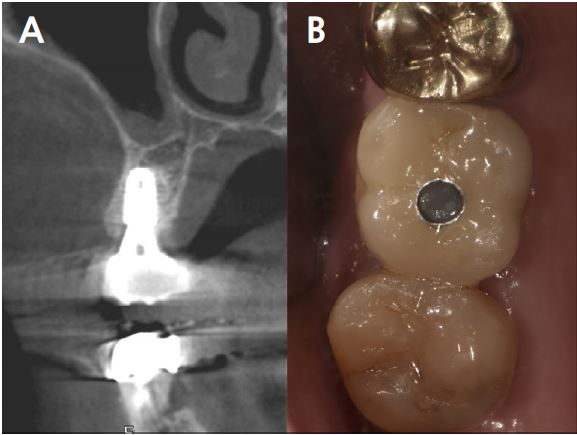

At 20 months follow-up, the cone beam computed tomography (CBCT) paraxial view showed that the buccal side of the fixture was adjacent to the outer border of the buccal bone plate (Fig. 5). However, the implant buccal probing depth (PD) did not exceed 4 mm, and the condition was maintained without any complications for 20 months after prosthesis placement (Fig. 6A, 6B).